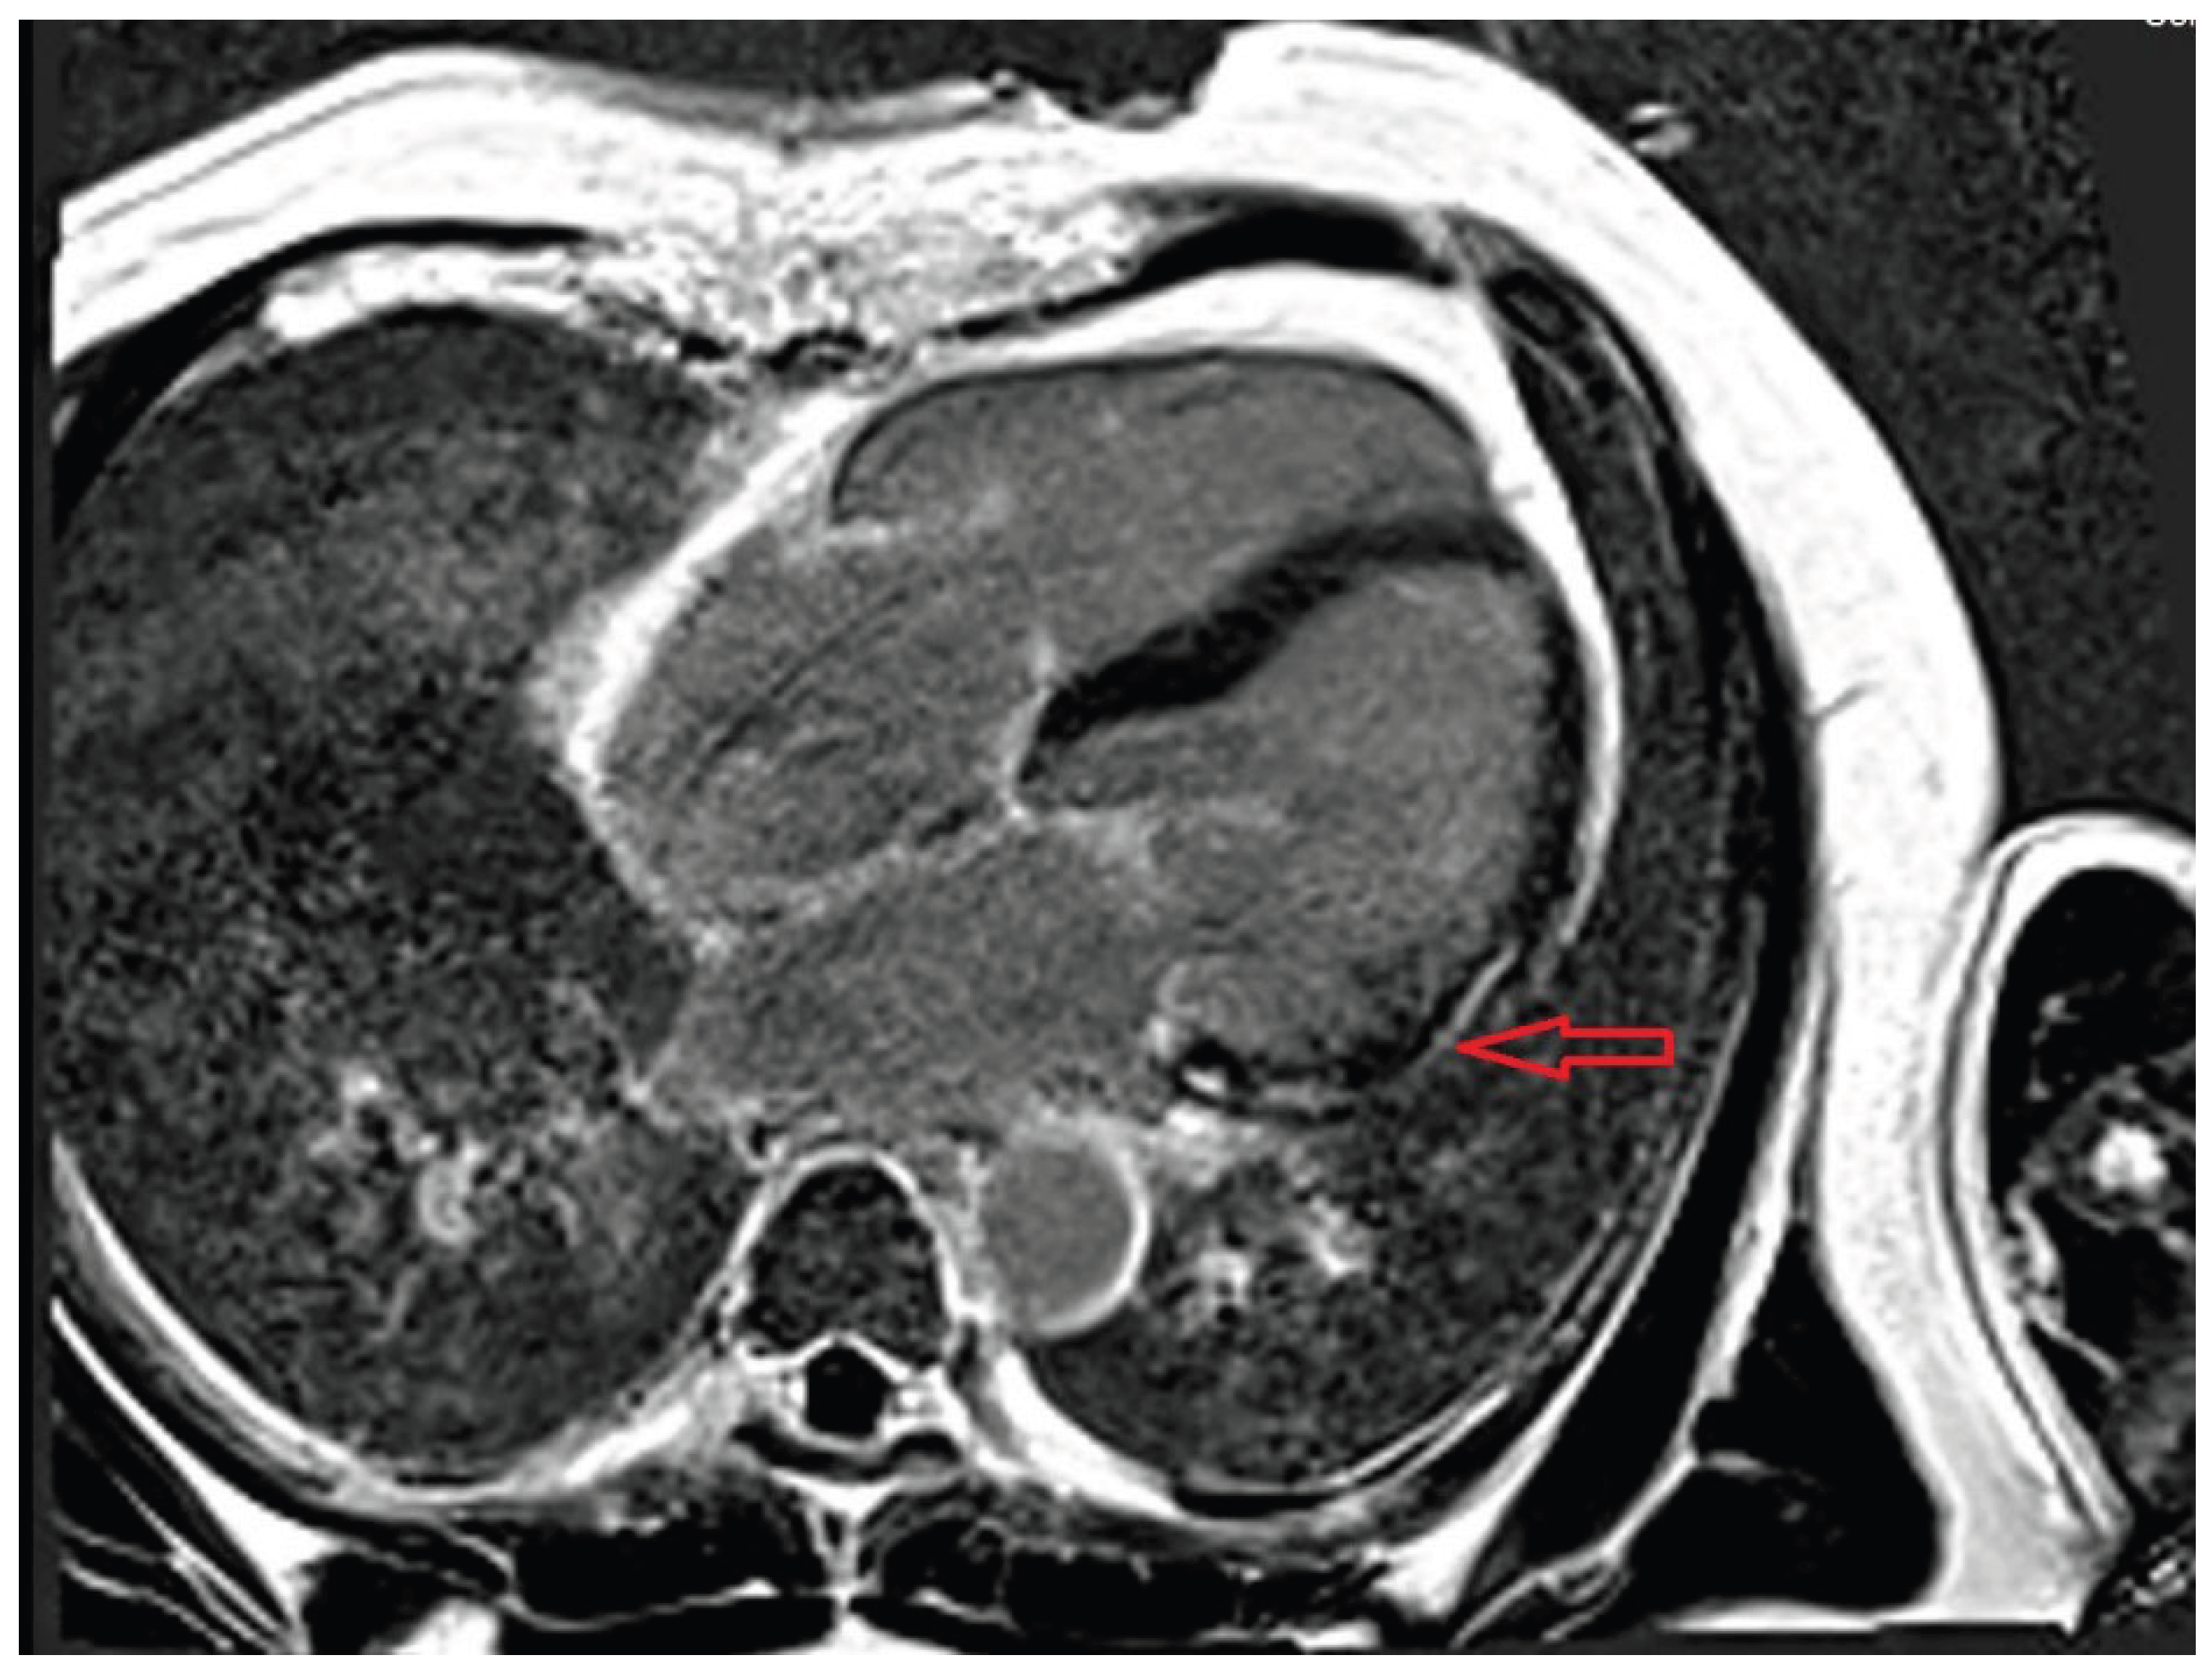

- Doeblin, P.; Jahnke, C.; Schneider, M.; Al-Tabatabaee, S.; Goetze, C.; Weiss, K.J.; Tanacli, R.; Faragli, A.; Witt, U.; Stehning, C.; et al. CMR Findings after COVID-19 and after COVID-19-Vaccination-Same but Different? Int J Cardiovasc Imaging 2022, 38, 2057–2071. [Google Scholar] [CrossRef] [PubMed]

- Ferreira, V.M.; Schulz-Menger, J.; Holmvang, G.; Kramer, C.M.; Carbone, I.; Sechtem, U.; Kindermann, I.; Gutberlet, M.; Cooper, L.T.; Liu, P.; et al. Cardiovascular Magnetic Resonance in Nonischemic Myocardial Inflammation: Expert Recommendations. J Am Coll Cardiol 2018, 72, 3158–3176. [Google Scholar] [CrossRef]